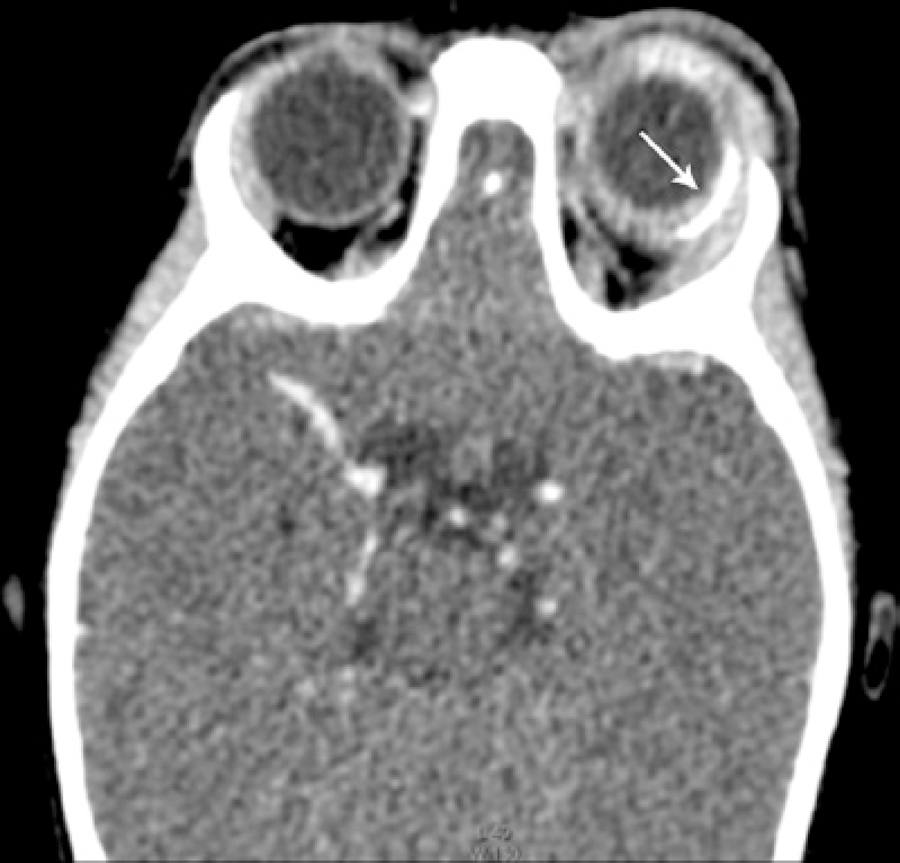

Computed tomography suggested infiltration of the periorbitary tissue, generalized scleral thickening, and increased density of the postseptal fat (Figure 1). Ultrasonography findings included low-amplitude mobile echoes, vitreous membranes, and thickening of the retina and choroid (Figure 2).

Figure 1 Orbital computed tomography demonstrated proptosis, inflammation of the extraconal fat, scleral thickening, and diffuse purulent collection surrounding the Ahmed™ glaucoma valve implant (arrow).

The patient was examined under anesthesia on the same day. Perioperative observations revealed a swollen, tense, and hyperemic superior eyelid. The OS was proptotic. The conjunctiva was chemotic and had significant hyperemia (3+/4), the cornea was diffusely hazy, and the anterior chamber had a large hypopyon. Neither the lens nor the ocular fundus could be visualized.